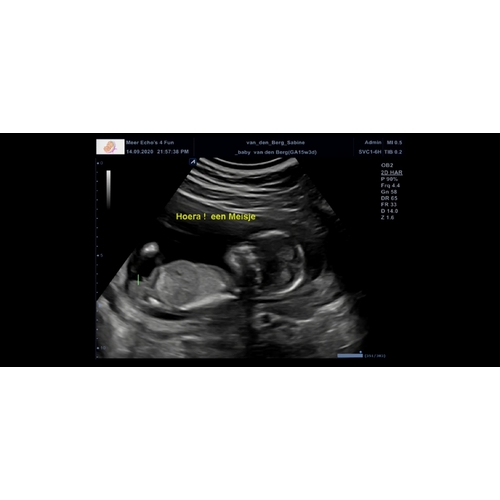

Dit is mijn echo foto van vandaag, mijn vriendinnen heb ik een envelop gegeven met het geslacht en ik weet het zelf ook niet. Vraag me ook af of mensen het geslacht kunnen zien na aanleiding van deze echo.

Die 3 streepjes zie je echt tussen de benen. Ik heb zelf 2 meiden. En bij e ...